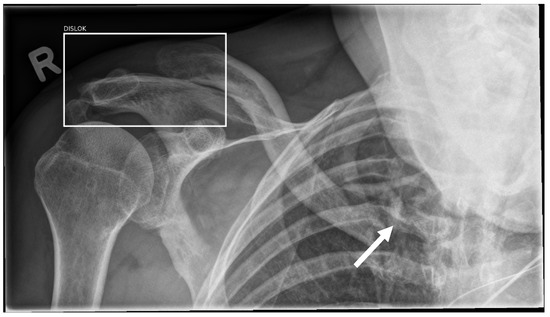

3.7. Effusion and Dislocation

| Shoulder/clavicle | 88.89% | 96.88% | 91.11% | 84.38% | 93.33% | 96.88% |